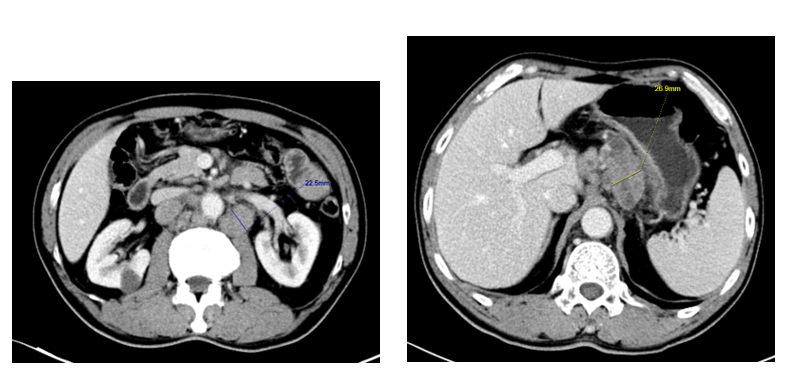

2022-05-30胸部平扫+增强CT;上腹部平扫+增强CT:两侧锁骨上、纵隔、肝胃间隙、腹膜后、膈肌脚后方多发肿大淋巴结,胃小弯侧壁显示增厚,建议胃镜。2022-05-30超声:双下颈、双侧锁骨上多发淋巴结肿大(转移性考虑),双侧腋窝淋巴结(转移性待排),甲状腺缩小伴回声不均。行超声引导下左侧锁骨上淋巴结粗针活检术,术后病理(202218301):(左侧锁骨上淋巴结)淋巴结转移性腺癌,以微乳头状生长。2022-06-02查胃镜示:胃体底CA累及贲门。胃镜病理示:(胃体)腺癌。免疫组化: hMLH1(+)、hMSH2(+)、hMSH6(+)、PMS2(+)、Her2(3+)、EBER(-)、CK7(+)、PD-L1(22C3)(CPS=1)。完善头颅MR未见转移灶。

于2022-06-13入组,2022-6-27至2026-2-12行第C1-C63治疗,具体用药:ZW25 1800mg+替雷利珠单抗200mg d1+奥沙利铂 130mg/m2 d1+卡培他滨 1000/750/500mg/m2 bid po d1~14, Q3W。(C7起停用奥沙利铂,因甲沟炎下调卡培他滨剂量)。

影像学评估:部分缓解(PR)

本文分享的患者为PD-L1低表达(CPS=1)、初治时已属IV期伴远处转移,属于传统治疗预后不佳的人群。然而,在加入HERIZON-GEA-01研究后,患者快速缩瘤,虽然从2023年起CEA水平有所升高并超出正常参考值上限,但其后的多次影像学复查(直至最近一次2026年2月)均保持PR状态,未见明确进展征象,已获得了超过44个月的超长PFS。这强有力地印证了临床研究数据,表明“泽尼达妥单抗+替雷利珠单抗+化疗”方案能够诱发深度且持久的治疗应答,甚至让部分晚期患者获得类似慢性病管理的长周期生存效益,这是肿瘤治疗追求的重要目标。